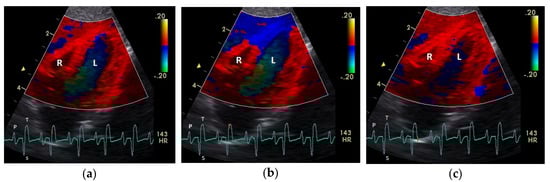

Figure 1.

Color coding of early (a) and active diastolic (b) tissue velocities and a part of the myocardial movement during the isovolumetric contraction (c) by tissue Doppler imaging in the four-chamber view: the movement of the myocardium toward (red color) and away from the heart apex (blue color) is visible. R: right; L: left ventricle; HR: heart rate. Electrocardiogram: P: P wave; S: S wave; T: T wave. The color scale on the right of the image is calibrated in cm s−1.

Color coding of the early (a), middle (b), and late part (c) of systolic tissue velocities by tissue Doppler imaging from the four-chamber view: the movement of the myocardium toward (red color) and away from the heart apex (blue color) is visible. R: right; L: left ventricle; HR: heart rate. Electrocardiogram: P: P wave; S: S wave; T: T wave. The color scale on the right of the image is calibrated in cm s−1.

The positive S’ wave of the TDI curve (Figure 3 and Figure 4; ascending part of the S wave to the descending part of the T wave of the ECG) describes the systolic movement of the heart base toward the heart apex and represents the expulsion phase of the heart. In the middle of the S’ wave of the TDI, there is little movement of the heart apex toward the heart base and the myocardial velocities are negative (Figure 2). This movement in the middle part of the systole led to an irregular shape of the S’ wave in the TDI curve (Figure 3). The negative E’ wave (Figure 3 and Figure 4; after the T wave of the ECG) in the TDI curve describes the movement of the myocardium during the passive ventricular filling and the second negative A’ wave of the TDI curve (Figure 3 and Figure 4; P wave of the ECG) describes the movement of the myocardium in the active filling phases of the heart during the diastole away from the heart apex. Before and after the S’ wave, the TDI curve showed undirected deflections as a sign of isovolumetric contraction (IVC) and relaxation (IVR; Figure 3 and Figure 4). However, the transition between the A’ and S’ waves (IVC) and the S’ and E’ waves (IVR) could be flowing and sometimes difficult to see.